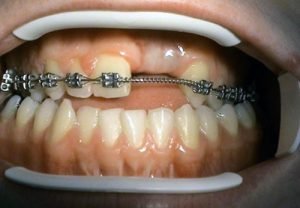

Implantation solution of the posterior toothless sections in the jaw

Solution of frontal defect in the jaw

Solution of frontal defect in the jaw in a jaw orthopedic anomaly